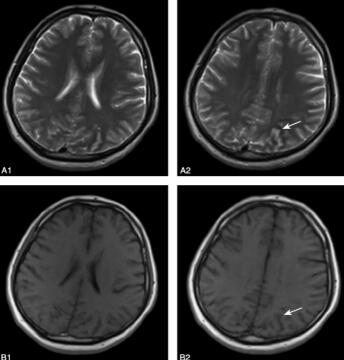

2011年6月1日(距发病后20小时)第一次行MRI提示:左顶下小叶见斑片状低T1、高T2信号影,FLAIR呈高信号,占位效应不明显,提示脑梗死或脑炎可能(图1)。2011年6月2日行MRI增强扫描提示:平扫所见左枕顶叶异常信号灶处见脑沟局限性轻度增宽及局限脑实质、脑膜小片状轻度强化,提示左枕顶叶局灶性脑炎。

图1 2011年6月1日行MRI示:在左顶下小叶附近见斑片状异常信号,占位效应不明显,主要累及白质;A1.T2WI双侧基底节区及放射冠区未见异常信号;A2.T2WI在左侧顶下小叶可见小片状呈高信号影(箭头);B1.T1WI双侧基底节区及放射冠区未见异常信号;B2.T1WI在左侧顶下小叶可见小片状呈略低信号影(箭头)